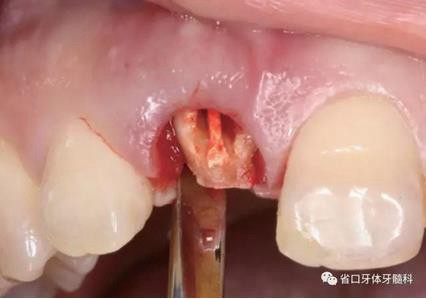

圖8 刮除肉芽組織

圖9 探測(cè)唇側(cè)骨壁完整

(1)微創(chuàng)拔牙及即刻種植:術(shù)前拍攝口內(nèi)照及實(shí)施牙周基礎(chǔ)治療。常 規(guī)消毒鋪巾阿替卡因局麻下微創(chuàng)拔除上頜右側(cè)中切牙,搔刮拔牙窩及根尖肉 芽組織。探測(cè)牙槽骨唇側(cè)骨壁及鄰面牙槽嵴完整,牙齦無(wú)撕裂。不翻瓣下于上頜右側(cè)中切牙缺隙近遠(yuǎn)中中點(diǎn)的腭側(cè)牙槽骨及根方定位,按照逐級(jí)預(yù)備的原則,緊貼牙槽窩腭側(cè)骨壁制備種植窩洞,植入Zimer®3.7mm×13mm TSV種植體1顆,植入扭矩>35N·cm,以O(shè)sstell測(cè)量種植體的ISQ值為68。 種植體平臺(tái)位于唇側(cè)齦緣中點(diǎn)下3mm,與唇側(cè)骨壁內(nèi)側(cè)面形成的跳躍間 隙約2mm,置入Bio-Oss®細(xì)顆粒骨粉0.25g,上愈合基臺(tái)關(guān)閉創(chuàng)口。術(shù)后 CBCT檢查顯示:種植體利用牙槽窩根方骨質(zhì)固位,緊貼牙槽窩腭側(cè)骨壁, 其唇側(cè)面與牙槽窩唇側(cè)骨壁的內(nèi)側(cè)面所形成的跳躍間隙(約2mm)可見(jiàn)顆 粒狀顯影物充填。牙槽窩的唇側(cè)骨壁及唇側(cè)倒凹無(wú)缺損穿孔。